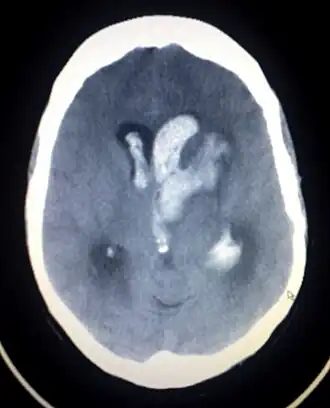

CT scan van een spontaan intracerebraal hematoom

Intracerebraal hematoom

Intracerebraal hematoom is de medische aanduiding van een bloeding, waarbij het bloed zich in het hersenweefsel bevindt. Dit is de meest voorkomende hersenbloeding en deze treedt spontaan op. De gevolgen voor de patiënt zijn ongeveer hetzelfde als bij een herseninfarct. De belangrijkste oorzaak is hoge bloeddruk, dus hypertensie. Dit is de enige vorm die een echte 'hersenbloeding' mag heten.